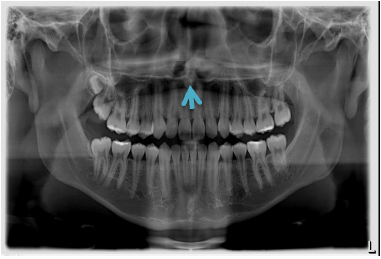

Sobre a anatomia radiográfica, identifique a seguinte estrutura: